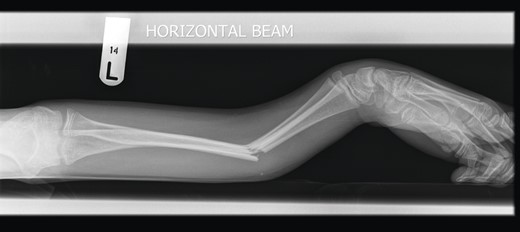

A 12-year-old male patient sustained a closed midshaft both-bone forearm fracture of their non-dominant arm from a fall on a trampoline (Figs 1 and 2). Anatomical reduction was achieved with a manipulation under anaesthesia (MUA), but it was noticed that there was a mechanical block to extension of the ring finger. The radius and ulna were therefore approached through separate incisions and it was discovered that the FDP was entrapped at the ulna fracture at the level of the musculotendinous junction. Following release the fingers regained a full range of motion and the patient went on to heal without further complication (Figs 3 and 4).

Pre-operative lateral radiograph showing dorsally angulated both-bone forearm greenstick fracture.